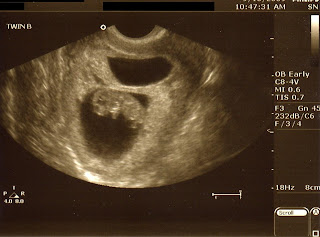

Letting out a sigh of relief (while still entirely overwhelmed) that we saw two perfect little babies. Strong heartbeats, and inch-long bodies jumping around with all the enthusiasm of early life.

The other day, I looked in the mirror and recoiled in horror to see how ENORMOUS my stomach is already, for being so early in the pregnancy. I shared with DH my fear that I am pregnant with a freakish Twilight vampire baby (make that two) that gestates to maturity in only three months. Unfortunately, he did nothing to calm my worries by heartily agreeing that could be a possibility, given my girth. I felt a little bit better today when the twinklets were measuring a full week ahead, making me 10 weeks along instead of 9 weeks.

Revised due date: April 16, 2010